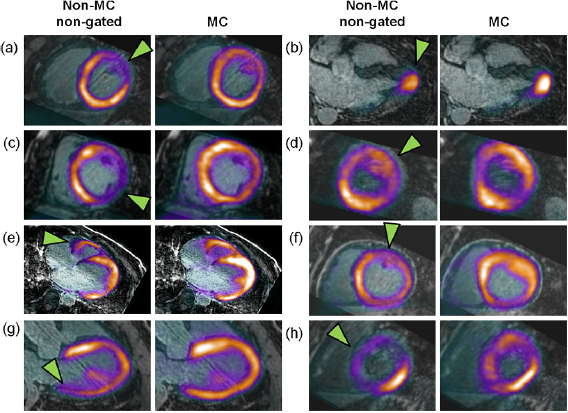

MC and non-MC non-gated PET images showed qualitative differences upon inspection of tracer uptake in the myocardium (figures 2 and 7). Areas affected by motion were easily identified, appearing blurred and wider than other areas of the myocardium. Among those areas, 20 areas were identified for analysis and occurred mostly in the anterior and lateral walls of the myocardium (table 1). After motion correction, areas affected by motion were noticeably more focal and qualitatively aligned better with the underlying anatomy of the myocardium when fused with MR images that were acquired in the reference end-expiration late-diastolic phase (figure 7). Double-gated images showed a similar pattern of more focal tracer distribution but were limited by an overall reduction in SNR (figure 7). PET/MR images before and after motion correction for all eight patients are shown in figure 8.

Standard image High-resolution imageFigure 8. Motion-corrected PET/MR. Fused non-MC non-gated PET/MR images and MC-PET/MR images in all eight patients (a)–(h) showing regions most affected by motion (arrowheads).